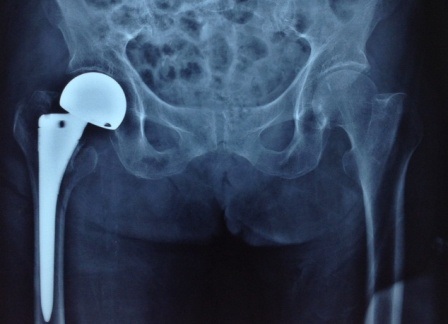

Ca phẫu thuật thay khớp háng nhiều rủi ro đã thực hiện hành công

Sau hai tuần điều trị hậu phẫu thay khớp háng lưỡng cực không xi măng bệnh nhân đã bình phục tốt và vận động được chân bên phải. Đây là một phẫu thuật lớn có nguy cơ tử vong trong và sau mổ rất cao do các biến chứng của tim mạch, nhồi máu cơ tim và thuyên tắc phổi… nhưng đã được bệnh viện 115 thực hiện thành công.